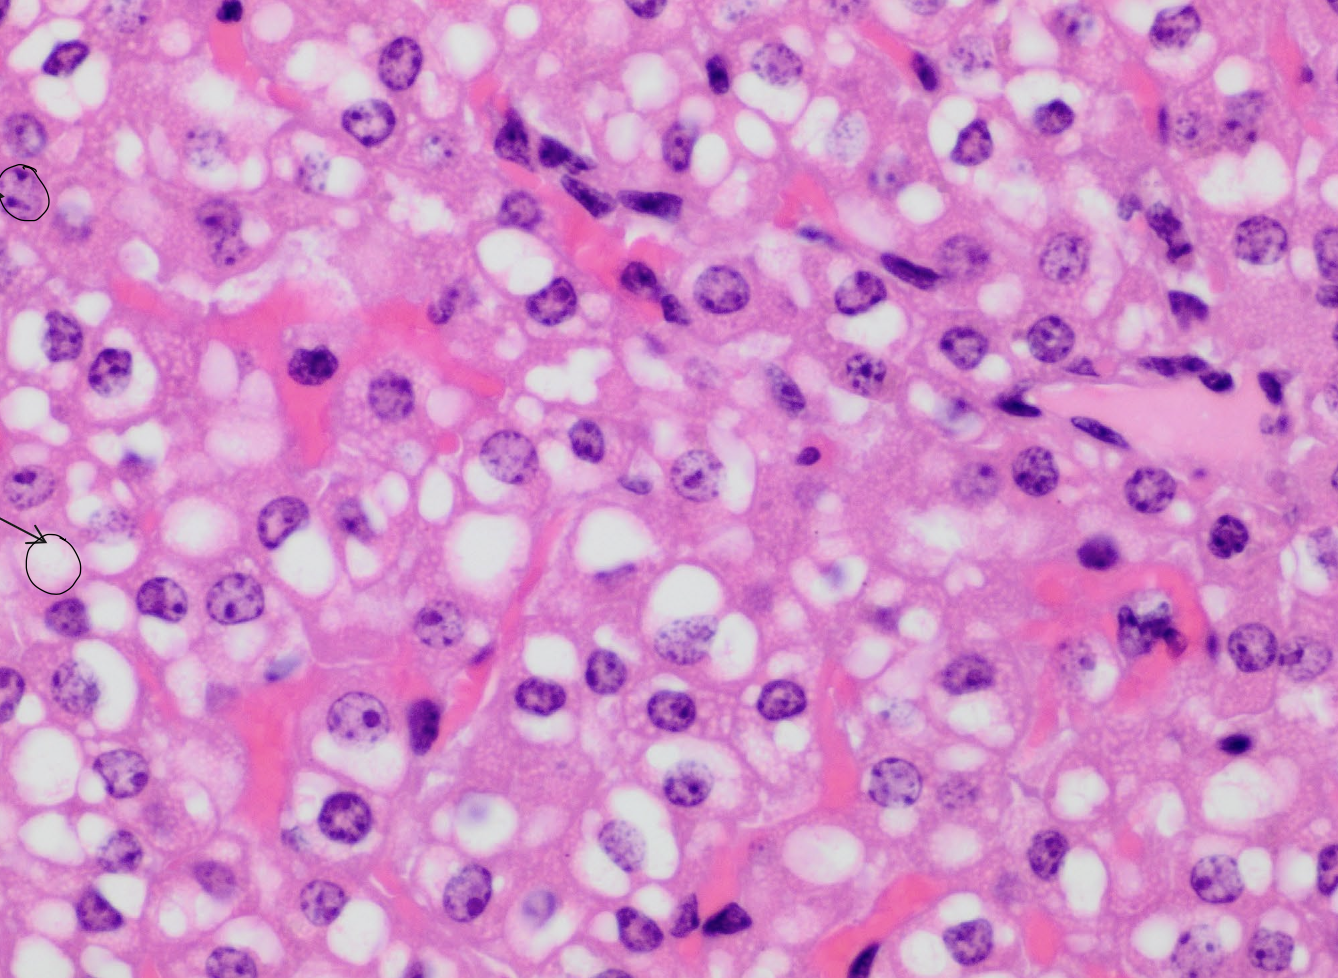

what are the neon pink spots?

hepatocyte sinusoids

what are the purple spots?

hepatocyte nuclei

what are the white spots?

lipid vacuoles within hepatocytes